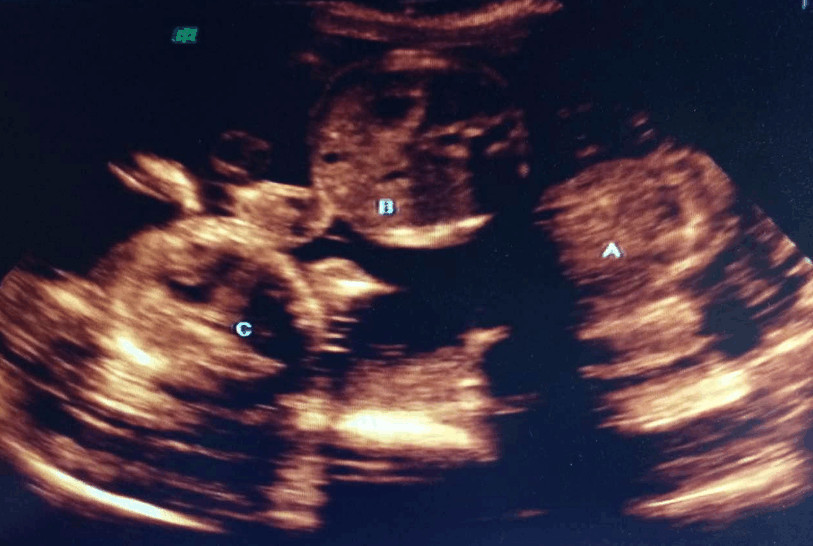

当婆婆知道娜娜怀孕后,十分的开心,每天都在弄好吃的给娜娜, 奇怪的是娜娜孕期的反应几乎没有,而且胃口十分的好,到了三个月的时候,娜娜的肚子已经十分的大了,明眼人一看就知道是个多胞胎。于是三个月的时候去医院产检,查出来是四胞胎的时候,婆婆直接愣住了,老公当场傻了。